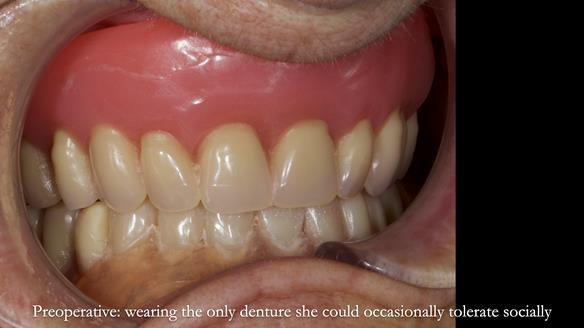

Welcome to Newsletter 83. This month I am sharing Sheila’s case — a very challenging but rewarding complete denture case. Sheila had flat ridges, a small mouth opening, a large tongue and had never been able to wear complete dentures of any kind. Everything was loose and sore. She felt embarrassed and looked older without dentures. She wanted a stable, comfortable result, and she wanted to avoid implants because she has taken bisphosphonates for more than five years.